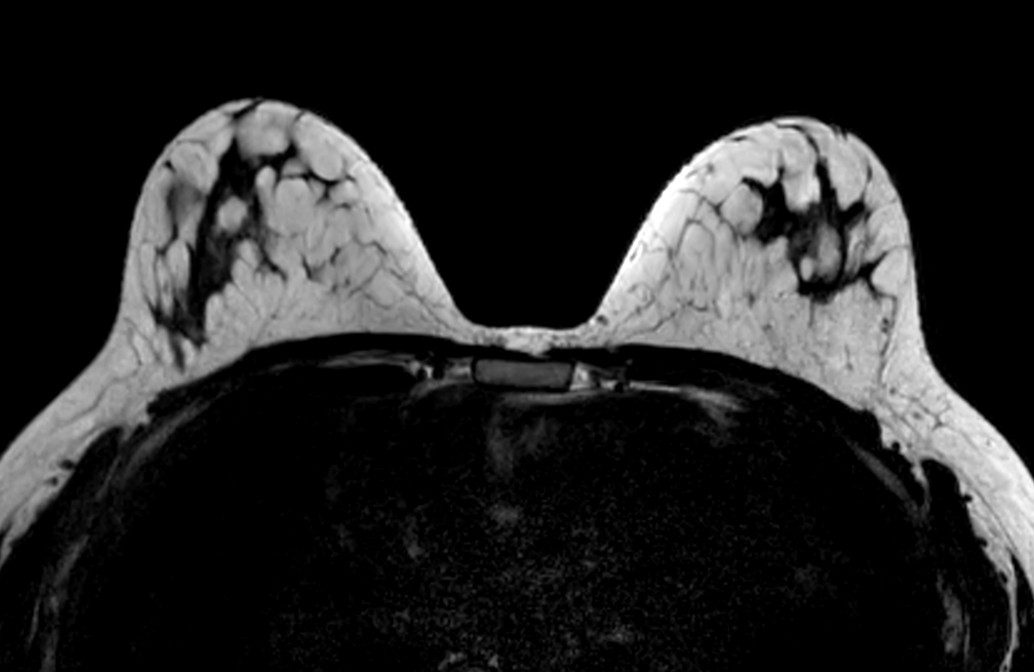

Axial T2w TSE